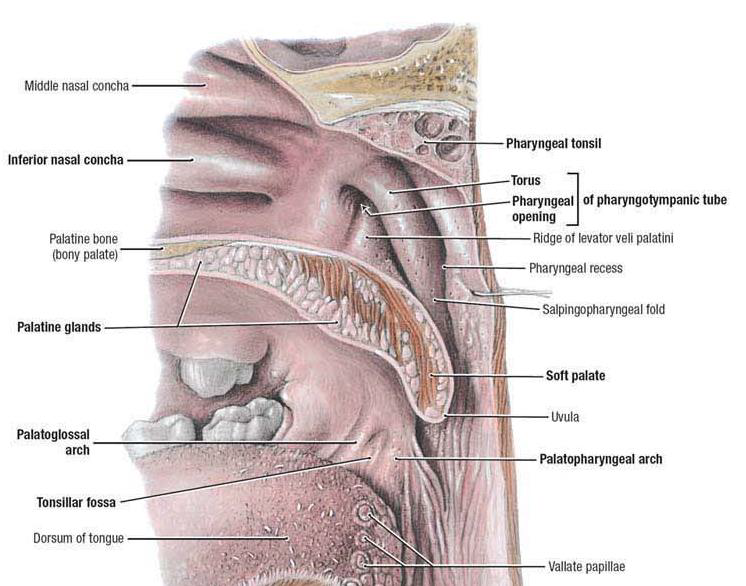

Structure

Nasopharynx

Sensor:CN V

- Opening of Pharyngotympanic tube (auditory tube, Eustachian tube)

- 前:Salpingopalatine fold

- 後:Torus tubarius Salpingopharyngeal fold

- Pharyngeal tonsil

Pharyngotympanic tube

- 通過 Temporal bone

- 後2/3是軟骨

- 通過 Temporal bone

- 後2/3是軟骨

Oropharynx

Sensor:CN IX

由外而內

- Palatoglossal fold(arch)

- Palatine tonsil

- Palatopharyngeal fold(arch)

- 分隔口腔與口咽(fauces)